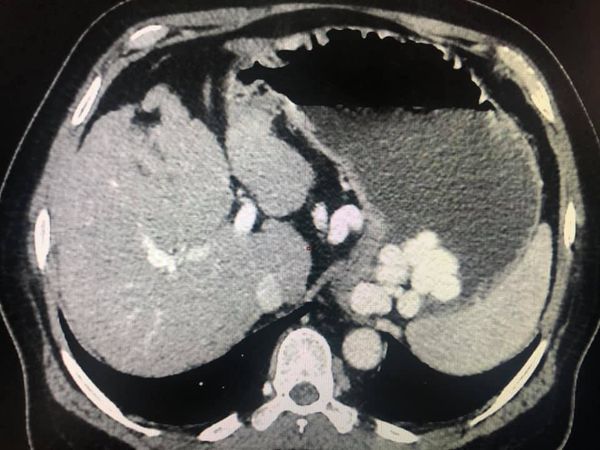

With chemotherapy improved survival with quality of life for Stage 4 cancer patient

Interesting Images March 2019 : Patient came with an early stage carcinoma rectum, underwent Hemicolectomy surgery then lost to follow-up. Later after 9 month patients presented to us with Stage 4 disease (Carcinoma colon with Liver secondaries). Then we started her on treatment with Chemotherapy along with Monoclonal antibodies with six cycle of above said treatment patient achieved near complete remission. We could achieve very good results with chemotherapy even in patients with Stage 4 disease (Carcinoma colon with Liver secondaries).